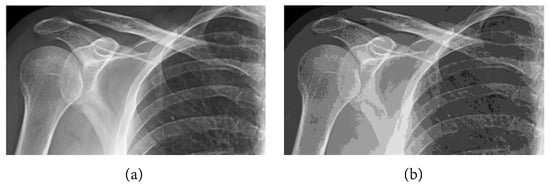

The following numerical results are proposed: Figure 2 presents the original grayscale images for (a) X-ray film of the brain and (b) X-ray film of the right shoulder. Figure 3 and Figure 6 are blurred X-ray films of the brain and the right shoulder images with filtering M i x in the part of degradation of Figure 1. In this example, we set N = 4 . So, we have M 1 x , M 2 x , M 3 x , and M 4 x . Figure 4a, X-ray films of the brain and the right shoulder images were obtained via Theorem 2. Figure 4b, X-ray films of the brain and the right shoulder images were obtained via Theorem 3.1 in [16] (Khuangsatung and Kangtunyakarn’s method). Figure 9 is an X-ray film of the brain image that was recovered via the proposed method that was tuned for the parameter λ.

Figure 6. Blurred X-ray film of the right shoulder image with filtering M i x by (a) M 1 x , (b) M 2 x , (c) M 3 x and (d) M 4 x .

Figure 7. (a) X-ray film of the right shoulder image obtained via Theorem 2 and (b) X-ray film of the right shoulder image obtained via Theorem 3.1 in [16].